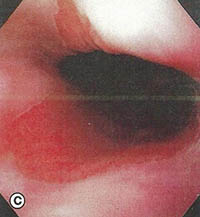

Υποψία για οισοφάγο Barrett τίθεται κατά την ενδοσκόπηση και πιστοποιείται με βιοψία και ιστολογική εξέταση. Φυσιολογικά το επιθήλιο του στομάχου είναι κυλινδρικό και η γαστροοισοφαγική συμβολή (Z-line), ευρίσκεται, κανονικά στο κατώτερο άκρο του οισοφάγου, ακριβώς πάνω από τις εγγύτερες πτυχώσεις μιας μικρής διαφραγματοκήλης, εάν αυτή είναι υπαρκτή.

Όμως στον οισοφάγο Barrett, ο άπω οισοφάγος επενδύεται με κυλινδρικό επιθήλιο, που επεκτείνεται προς τα πάνω για μία μεταβλητή απόσταση, συχνά από 3cm μέχρι 10cm αλλά και περιστασιακά εμπλέκει το μεγαλύτερο τμήμα του οισοφάγου. Το εγγύς όριο του οισοφάγου μπορεί να είναι οριζόντιο ή μπορεί να υπάρξουν ανώμαλες, συχνά σχήματος γλώσσας επεκτάσεις του κυλινδρικού επιθηλίου. Πολλοί ασθενείς έχουν νησίδια αναγεννητικού ή υπολειμματικού πλακώδους επιθηλίου, ενώ άλλοι παρουσιάζουν διάσπαρτα καλοήθη έλκη στην κυλινδρική περιοχή. Οισοφαγικές στενώσεις και οισοφαγίτιδα ίσως, να διαφαίνονται επί της ΝΕΑΣ συμβολής (πλακώδους – κυλινδρικού επιθηλίου). Επίσης, κατά την ενδοσκόπηση θα πρέπει να αναζητείται ένδειξη για αδενοκαρκίνωμα, όπως αυτή των οζιδίων ή μαζών.